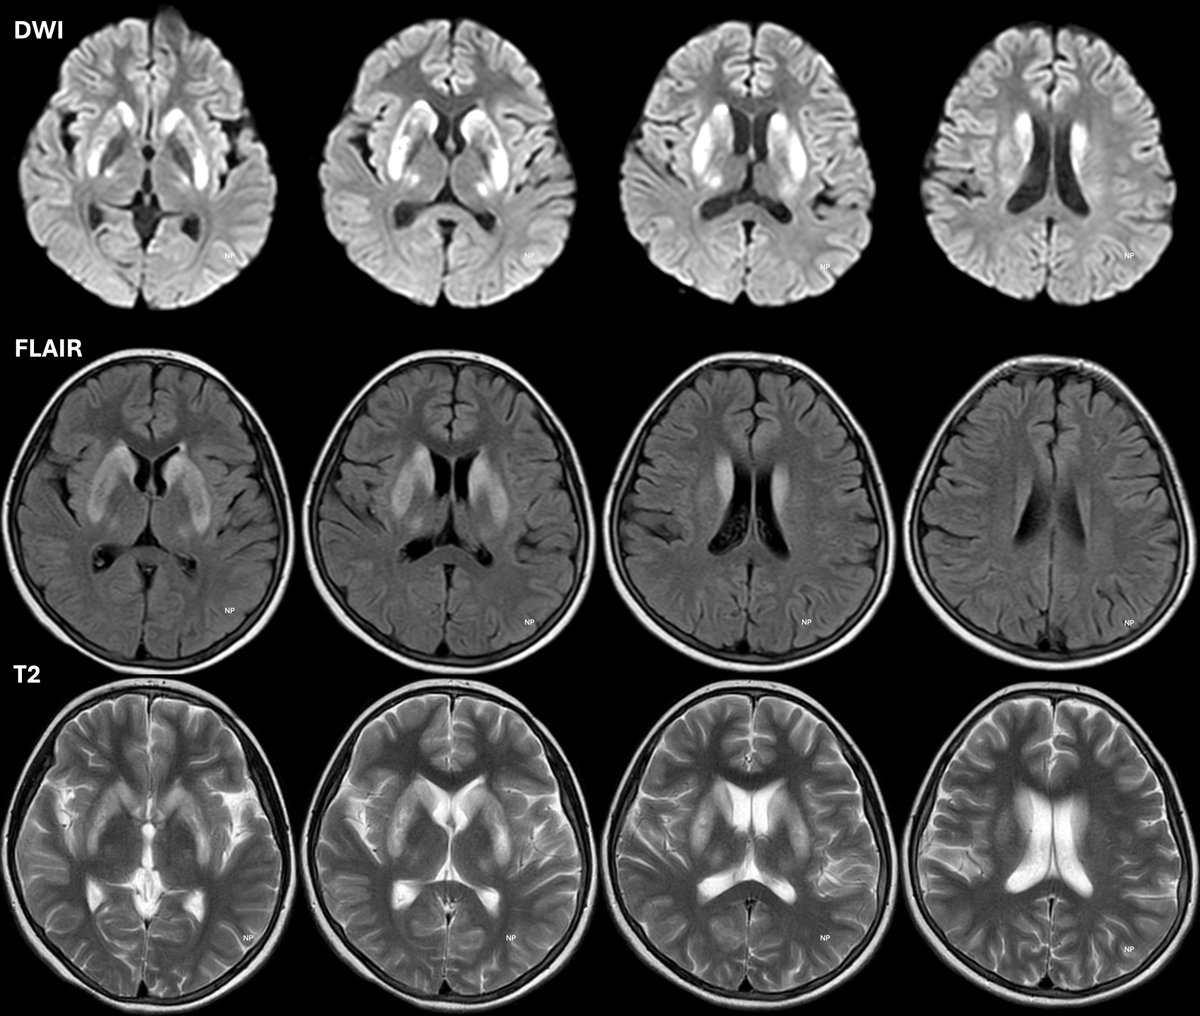

12♀ One month h/o of subacute parkinsonism syndrome Low volume difficult speech Staring look Sialorrhea Open mouth Extreme hypokinesia Fever 20 days before onset MRI πŸ‘‡

Diagnosis?

Additional history: H/o acute hepatitis 14 months earlier Hindu, born of consanguineous marriage ⚠️We often forget to ask for it in Hindus (range 9-28%) National average ~10% More common in South India Diagnosis is now simpleπŸ‘‡

β˜‘οΈ Yes Wilson Disease PUTAMEN is the most commonly affected & strongly correlated with dystonia & parkinsonism esp in younger kids

🐼🐼🐼 Giant Panda Baby Panda Miniature (cub) Panda Double Panda Bright Claustrum Split Thalamus Whorl Sign Cortex|Pons|Cerebellar involvement Epilepsies... Are probably less seen now with heightened awareness & cheaper test availabilities